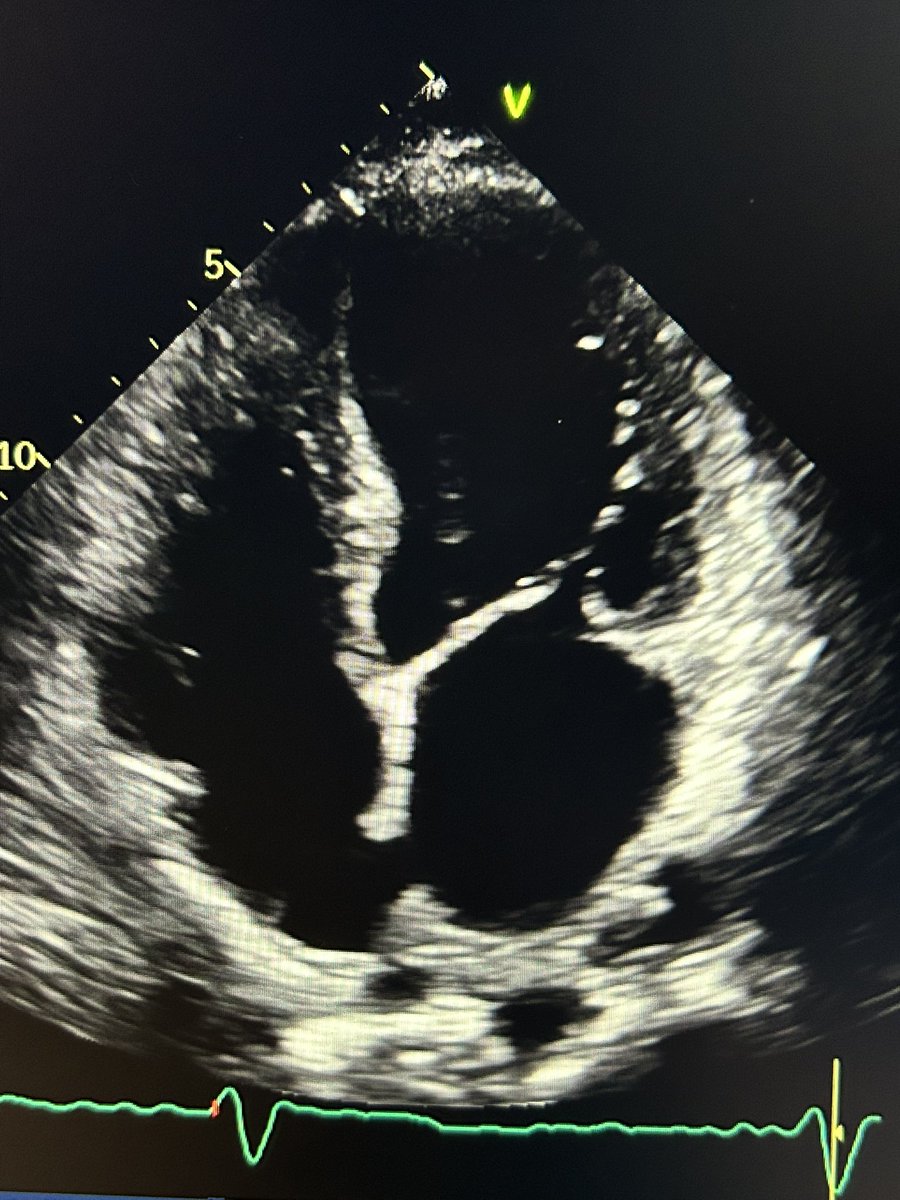

Ok, so let’s investigate.

Drop the depth, increase the frame rate, minor tilt … and what do you know?

A thrombus!